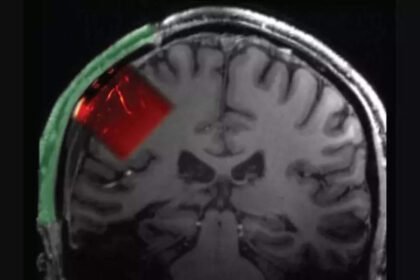

Scientists pioneer new ultrasound technology that can scan the brain |

A groundbreaking study has emerged from the intersection of neuroscience and technology,…